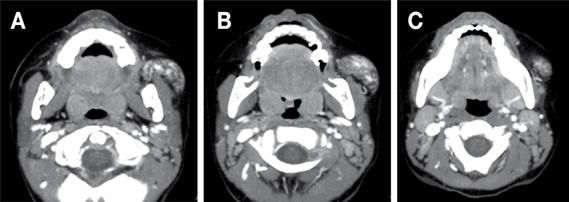

En la tomografía computarizada con contraste se evidenció en la región geniana izquierda, además de las regiones maseterina y pterigomaxilar, una lesión de densidad heterogénea, de predominio hipodenso, sugiriendo componente adiposo, de bordes definidos y delimitados por la fascia de los tejidos blandos vecinos, mide aproximadamente en su porción externa 32 x 17 x 29 mm (región geniano-maseterino) y su porción interna 18 x 13 x 28 mm (región pterigomaxilar), con un elemento vascular central importante, procedente principalmente de la arteria maxilar interna (Figura 3, 4 y 5).

Figura Nº3 . Vista axial de TAC que muestra masa heterogénea en las regiones geniana y maseterina izquierdas, anterior y lateral al músculo buccinador (A), lateral al músculo masetero (B) y que llega hacia abajo hasta el nivel del arco dentario mandibular (C).